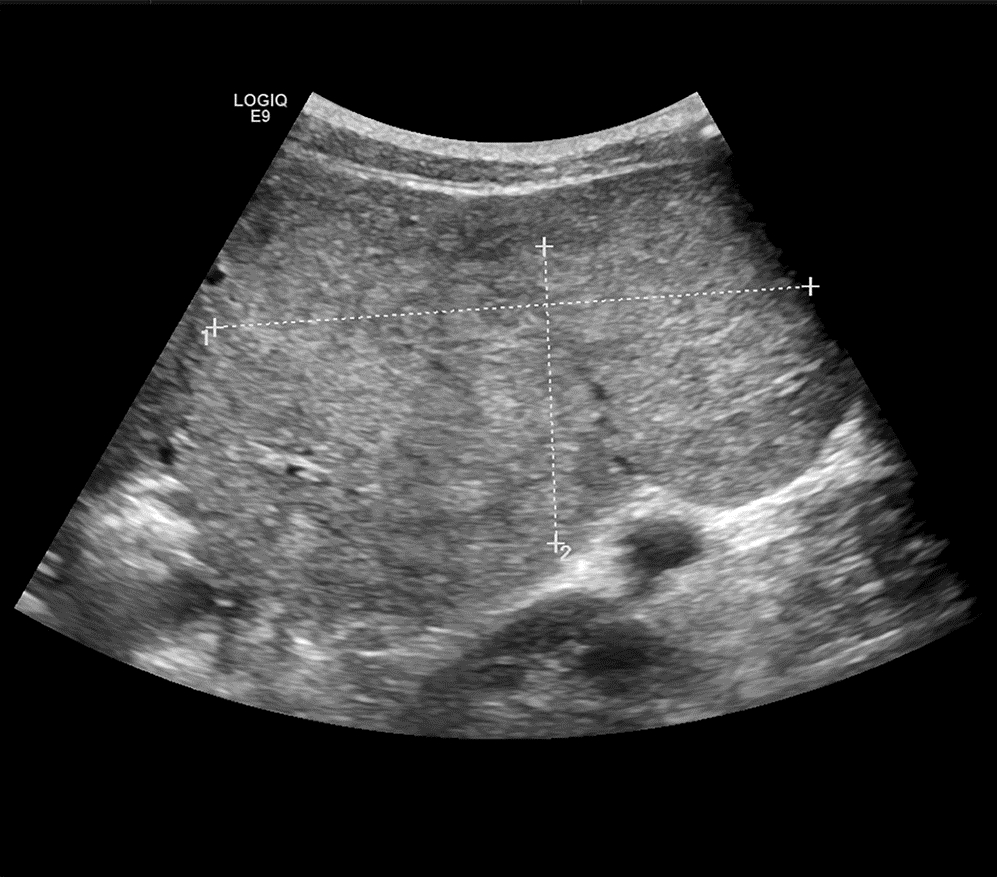

Ultrasound findings and contrast-enhanced ultrasound findings of mass-type autoimmune pancreatitis versus pancreatic ductal adenocarcinoma

Xiangliu OUYANG, Yunxia HAN, Lichun ZHENG, Yingchun ZHAO, Xinyu SHEN, Wenjun ZHANG, Yanbin WANG

2022, 38(6): 1351-1355. DOI: 10.3969/j.issn.1001-5256.2022.06.025

Abstract(1465) HTML (554) PDF (3738KB)(58)

Abstract:

Objective  To investigate the value of ultrasound and contrast-enhanced ultrasound (CEUS) in the differential diagnosis of mass-type autoimmune pancreatitis (AIP) and pancreatic ductal adenocarcinoma (PDAC).  Methods  A retrospective analysis was performed for the clinical data, ultrasound findings, and CEUS findings of 11 patients with mass-type AIP who were diagnosed in Tangshan Workers' Hospital from January 2015 to December 2020, and their characteristic manifestations were analyzed and compared with the data of 23 patients with PDCA. The chi-square test was used for comparison of categorical data between two groups.  Results  For the 11 patients with mass-type AIP, CEUS had a diagnostic accuracy of 63.64%, and all of these patients had hypoechoic single lesions; the patients with clear boundaries, regular morphology, pancreatic duct dilatation or cutoff, and blood flow signal accounted for 54.55%, 63.64%, 18.18%, and 36.36%, respectively, while in the PDCA group, such patients accounted for 30.43%, 34.78%, 78.26%, and 21.74%, respectively, and there was a significant difference in the presence or absence of pancreatic duct dilatation or cutoff between the two groups(χ2=11.089, P < 0.05), with no significant differences in the other indices (all P > 0.05). For the 11 patients with mass-type AIP, CEUS showed that 7 patients (63.64%) had hyperenhancement and 4 (36.36%) had iso-enhancement in the arterial phase, and 5 patients (45.45%) had hyperenhancement in the arterial phase and 6 (54.55%) had iso-enhancement in the venous phase; for the 23 patients with PDCA, 22 (95.65%) had hypoenhancement of lesions in both arterial and venous phases, and there were significant differences in the enhancement pattern in arterial and venous phases between the two groups (χ2=30.345 and 30.084, both P < 0.05).  Conclusion  The enhancement pattern of CEUS and the presence or absence of pancreatic duct dilatation or cutoff have a relatively high value in the differential diagnosis of mass-type AIP and PDCA.